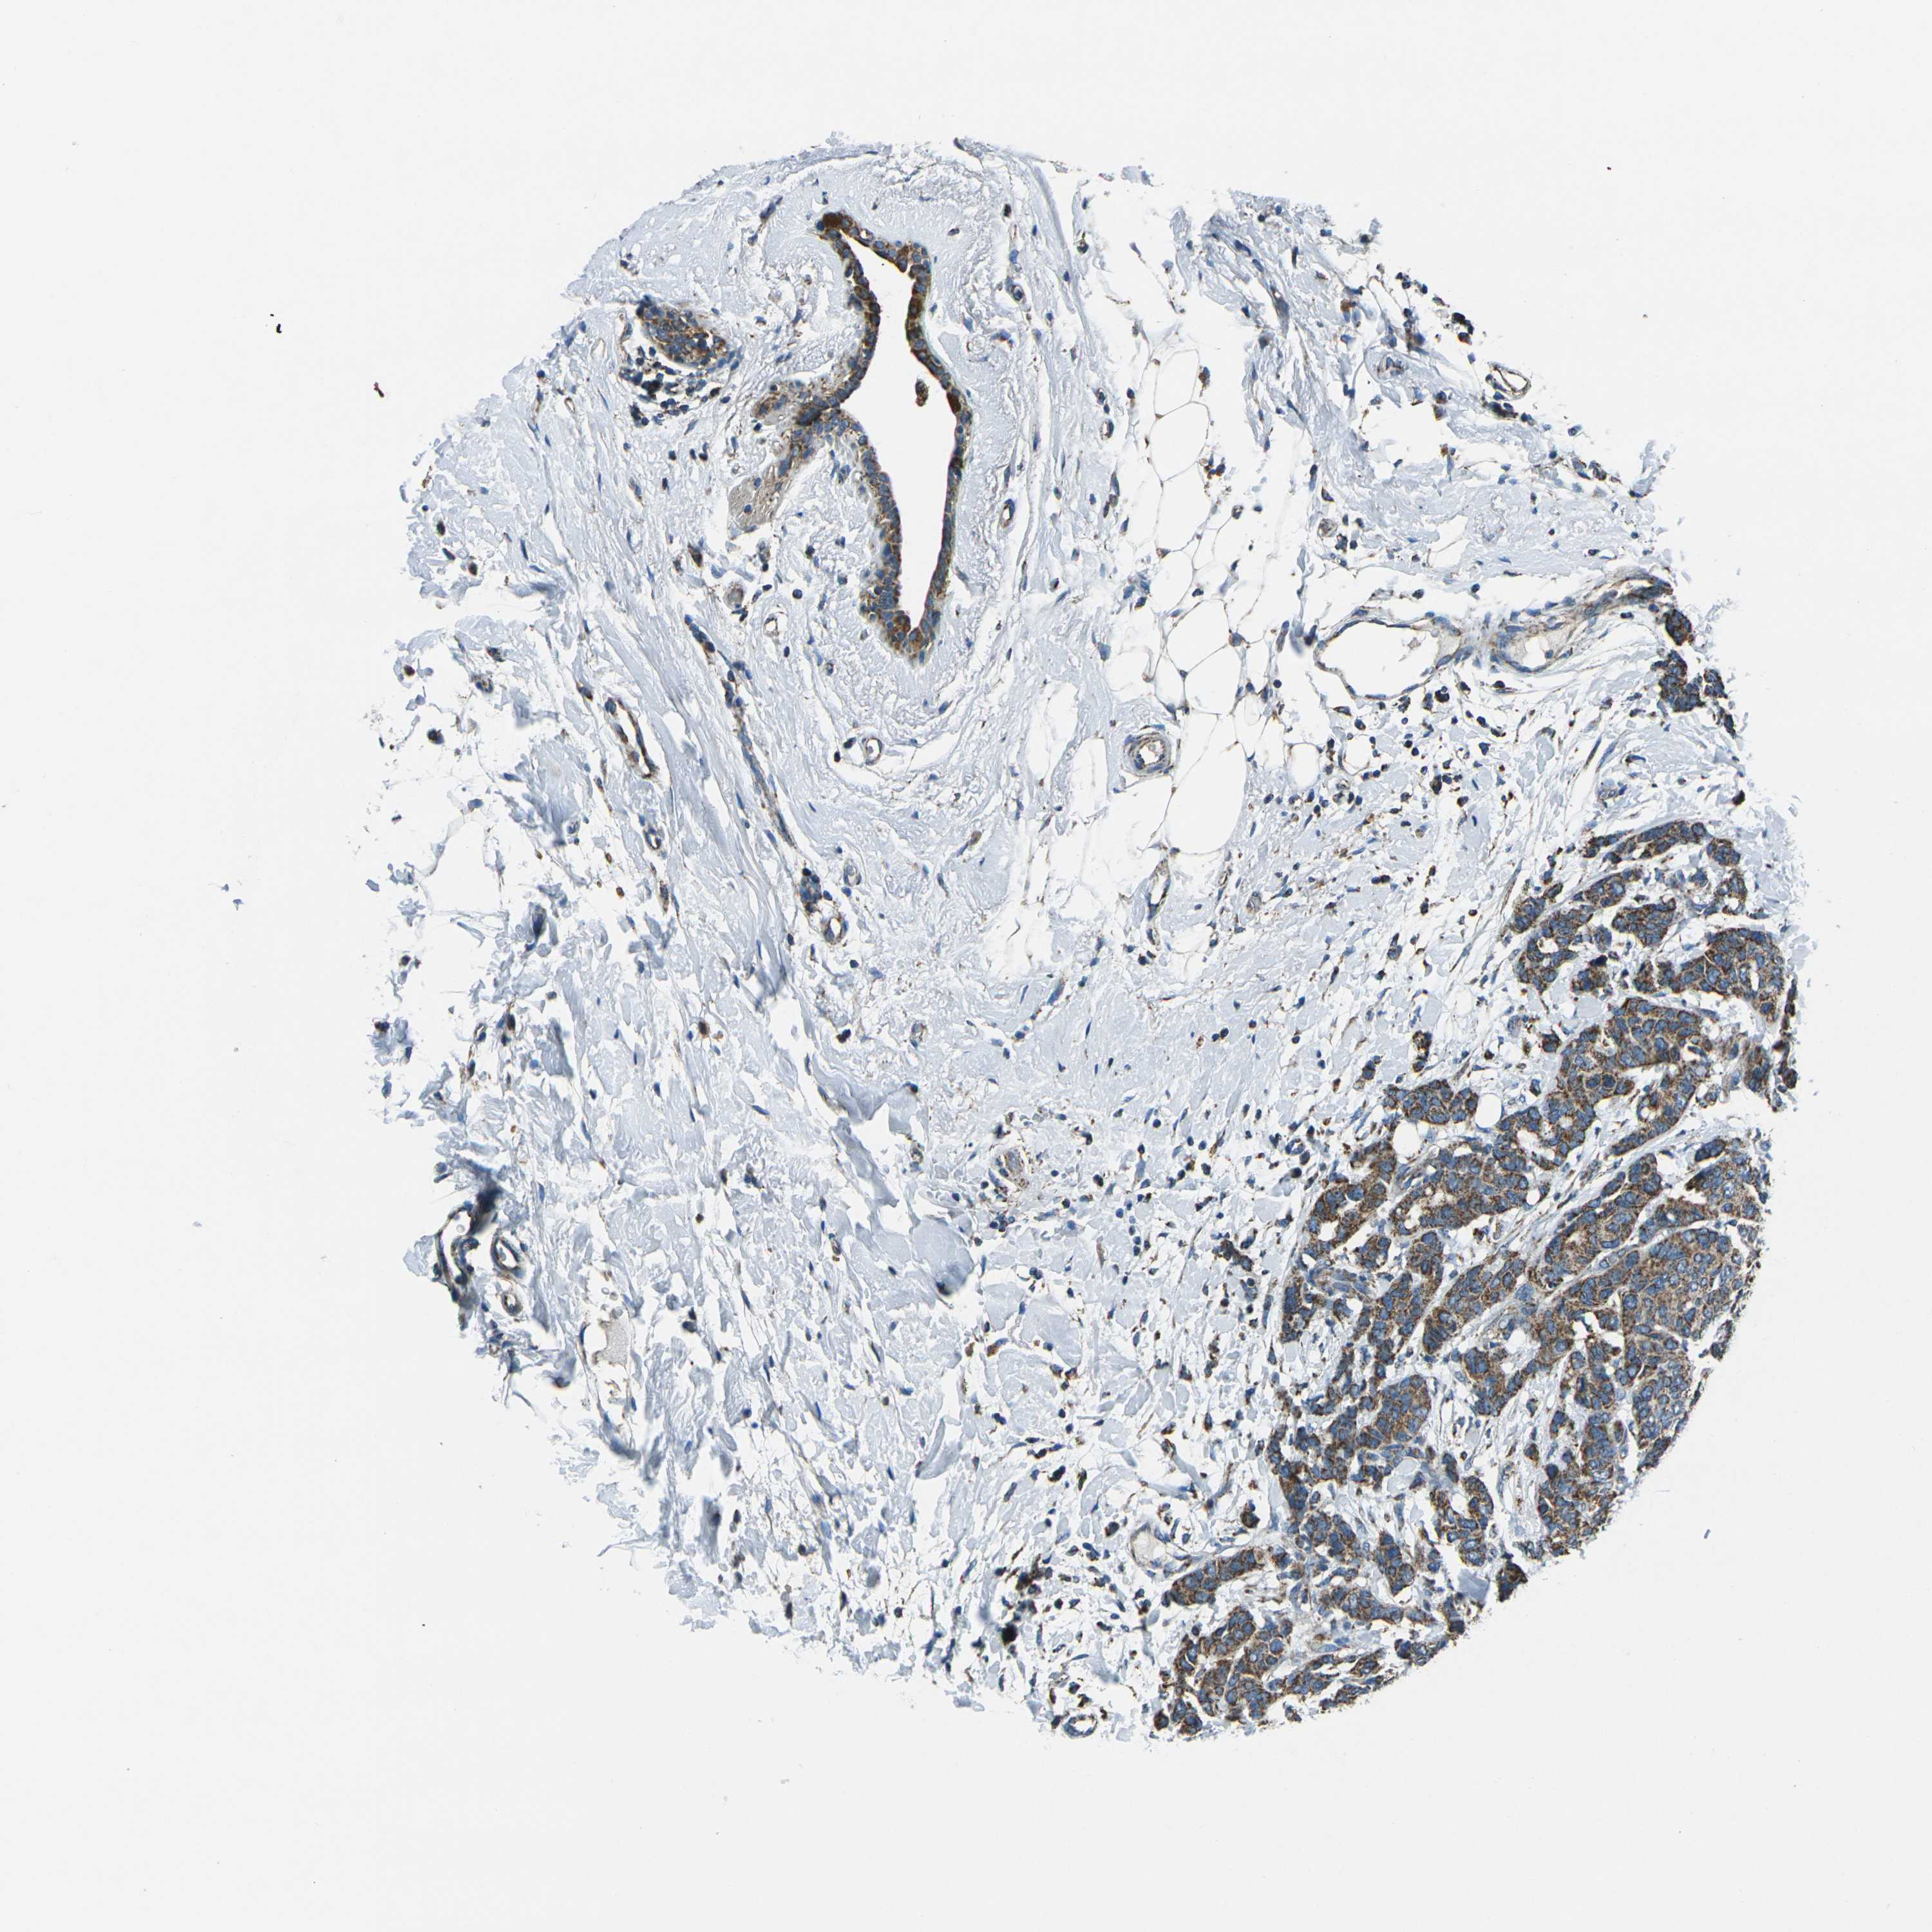

CANCER BREAST CANCER Show tissue menu

BRCA TCGA BRCA VALIDATION PROTEIN EXPRESSION

ANTIBODIES

AND

VALIDATION